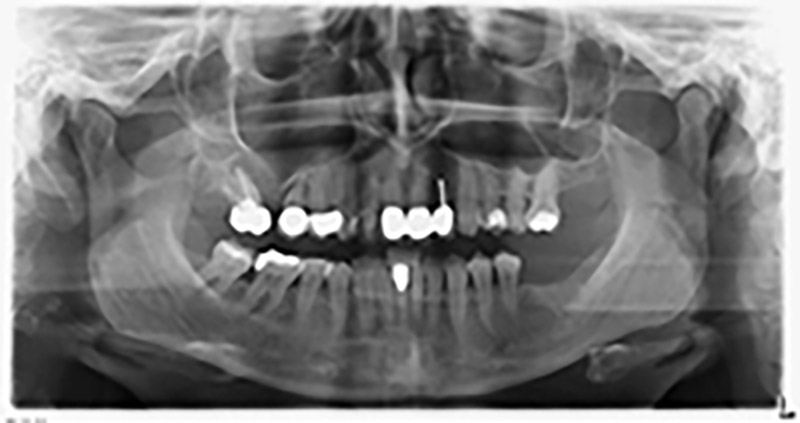

Unos seis meses después de la extracción de las piezas 16 y 14 se realizó una tomografía digital de volúmenes (DVT, Planmeca) para realizar una planificación adecuada y reducir los riesgos al mínimo. En este punto se constató que el hueso no se había regenerado en la cantidad deseada (figuras 2 a 7).

Con el fin de garantizar una restauración fija en al menos dos implantes, era preciso realizar una elevación del suelo del seno maxilar, tanto en la región 16 como en la región 14. Como en este caso la oferta de hueso residual era extremadamente reducida, fue preciso realizar una retirada ósea relativamente grande. Los procedimientos de retirada ósea grande son invasivos y, además, están asociados a una mayor morbilidad del paciente, llevan más tiempo y resultan más costosos. También es más difícil prever los resultados del tratamiento y el riesgo de fracaso es mayor. Teniendo como telón de fondo estas desventajas, la paciente recibió información sobre la posibilidad de utilizar una alternativa extraíble, pero ella la rechazó firmemente.